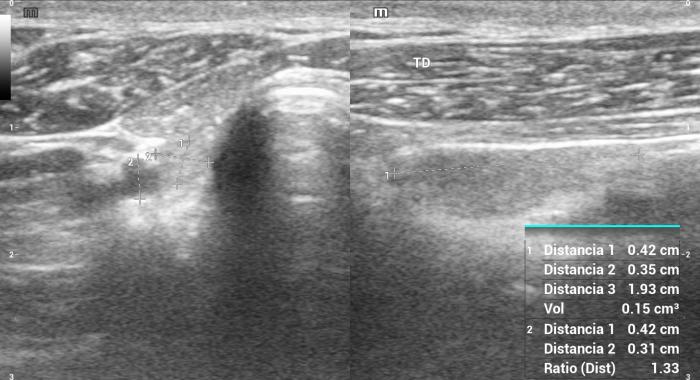

Relación entre el diámetro tiroideo (TD) y el diámetro de la arteria carótida común (CCA)

El uso de estructuras vasculares adyacentes como referencias anatómicas ha sido una estrategia útil en ecografía veterinaria para estandarizar las mediciones de órganos pequeños como la glándula tiroides. En este contexto, Bandula Kumara et al. (2019) propusieron la medición de la relación entre el diámetro tiroideo (TD) y el diámetro de la arteria carótida común (CCA) como una forma práctica de evaluar el tamaño de la glándula en perros clínicamente normales (Figura 5A-B).

Los autores realizaron un estudio en el que midieron el diámetro anteroposterior de los lóbulos tiroideos y el diámetro externo de la CCA en cortes transversales obtenidos a nivel del cuello medio. Encontraron que esta relación se mantiene relativamente constante entre razas y tamaños corporales, sugiriendo que puede ser utilizada como parámetro de referencia ecográfica. Específicamente, en perros adultos sanos, la relación TD/CCA fue de 1.74 ± 0.40 (rango 1.11–2.43)6. Si los valores se encuentran por debajo del rango normal pueden ser considerados potencialmente indicativos de hipoplasia tiroidea o atrofia glandular.

Una ventaja de esta relación es que la arteria carótida común es fácilmente identificable ecográficamente, presenta un diámetro estable y poco variable en condiciones fisiológicas, y se ubica en estrecha proximidad con la glándula tiroides. Esto la convierte en una excelente estructura de referencia para normalizar mediciones entre individuos de diferente tamaño corporal, permitiendo evaluaciones objetivas en poblaciones mixtas de perros de compañía.

Además, este índice podría tener aplicación clínica en el seguimiento de animales con enfermedad tiroidea subclínica o en tratamiento, ya que permite detectar cambios discretos en el volumen glandular con buena reproducibilidad interobservador. Aunque su utilidad clínica requiere aún validación en animales con patología confirmada, representa una herramienta complementaria valiosa dentro del enfoque ecográfico sistemático de la glándula tiroides en pequeños animales.